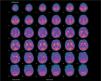

Presentamos el caso de una niña de 33 días de vida que ingresa por crisis convulsivas. Es la segunda hija de padres no consanguíneos. Amenaza de aborto en el primer trimestre. Parto y período neonatal sin incidencias. En las horas previas presenta episodios de hipotonía generalizada, cianosis facial y desconexión ambiental de una duración aproximada de 1min. A su llegada al hospital, la exploración física no revela anomalías. Durante el primer día se repiten las crisis en dos ocasiones y se inicia tratamiento con fenobarbital. El hemograma, bioquímica sanguínea y una ecografía cerebral no demostraron anomalías. El LCR en dos ocasiones mostró una glucorraquia de 15mg/dl, sin aumento de proteínas ni celularidad. Las cifras de lactato en el LCR se encontraban en el rango bajo de la normalidad. La glucemia antes de la punción lumbar fue de 93mg/dl, con un cociente glucorraquia/glucemia de 0,16. Una resonancia magnética cerebral mostró una pequeña lesión bilateral, en la cápsula externa hipointensa en T1 e hiperintensa en T2. En el surco central parietal se observa una pequeña zona de hiperseñal. La tomografía por emisión de positrones (PET) a nivel cerebral con fluorodesoxiglucosa (fig. 1) reveló una corteza cerebral con captación de glucosa globalmente disminuida, con un predominio aparente de la señal en los ganglios de la base e hipocaptación en los tálamos, sin lesión capsular acompañante detectable, junto con una disminución de la señal cerebelosa. Ante la sospecha de una deficiencia de Glut 1, se retiró el fenobarbital y se inició dieta cetogénica con un aporte de grasas del 60 %. El electroencefalograma (EEG) evidenció elementos agudos alternantes de predominio izquierdo. Tras la retirada del fenobarbital, no se observaron cambios significativos en la glucorraquia. En los primeros 4 meses de vida presentó episodios esporádicos de cese de actividad y fijación de la mirada de breve duración que no han recurrido tras el incremento del aporte de lípidos al 70 %. Con 14 meses, su desarrollo es normal y el crecimiento del perímetro craneal se mantiene en el percentil 50. Un nuevo análisis del LCR que reveló una glucosa de 29mg/dl. El estudio genético está en curso.

Nuestro caso se manifestó por convulsiones precoces, principal expresión clínica inicial del síndrome de deficiencia de Glut 12–4, aunque también puede cursar como un retraso mental asociado a disartria y ataxia intermitente sin epilepsia4,5 o, con menor frecuencia, por retraso en el desarrollo, coreoatetosis y distonía2,6. Se han descrito crisis generalizadas, tónicas o clónicas, mioclónicas, parciales, ausencias o atónicas como las que presentó nuestro paciente, así como crisis no clasificadas2,3,7. El EEG es inespecífico y con frecuencia no muestra anomalías7. Evolutivamente, la RM cerebral puede mostrar una hipotrofia cerebral y otras anomalías inespecíficas2,6 o de significado desconocido, como ocurrió en este caso. Una hipoglucorraquia con glucosa < 40mg/dl y un cociente de glucosa en LCR/glucosa en plasma ≤ 0,33 es altamente sugestivo de esta entidad en ausencia de infección o hemorragia subaracnoidea8. Los bajos valores de lactato en el LCR apoyan el diagnóstico. La concentración de glucosa en el LCR en el caso descrito es inferior a lo reflejado en la bibliografía2,6, y podría estar relacionado con una grave disminución del transporte de glucosa a través de la barrera hematoencefálica, que depende casi exclusivamente de Glut 1. El diagnóstico puede confirmarse mediante pruebas funcionales (captación de glucosa en eritrocitos o PET) y moleculares. La PET con aparente hipometabolismo difuso en la corteza y tálamo e hipermetabolismo aparente o relativo en los ganglios de la base es característica de esta entidad9. Es importante confirmar el diagnóstico del déficit de Glut 1, pues se han descrito formas de hipoglucorraquia transitoria en niños10. El tratamiento con FAES es ineficaz e incluso algunos fármacos pueden agravar el proceso2,3. El tratamiento con dieta cetogénica es efectivo en el control de las crisis2,3, aunque para algunos autores la utilidad en los déficits cognitivos es escasa2,3. Nuestra paciente con 14 meses de edad presenta un neurodesarrollo acorde con su edad cronológica. Consideramos que debe descartarse esta entidad ante una epilepsia de comienzo precoz y escasa respuesta a FAES, y debe incluirse en el diagnóstico diferencial del retraso mental no filiado.